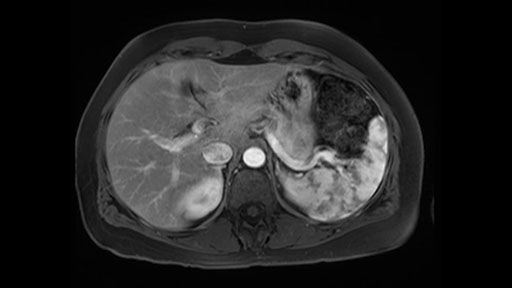

In reviewing this patient’s CT scan, first of all, the lesion is again cystic with a very thin wall. I anticipate that it will be delicate and potentially friable. And therefore the risk of rupture exists and we need to be very careful in how we handle the pancreas and the tumor throughout the procedure.

The lesion itself is quite adjacent to and abuts the splenic vein and therefore we need to anticipate that these two structures will be intimately related and possibly impossible to separate between the two.

The lesion also is quite posterior. While the plane between the cyst and the left adrenal gland is often preserved, we do have to pay attention here so that we remain in the right plane and maintain our margin here. Occasionally in these cases, en bloc adrenalectomy needs to be performed.

In terms of maintenance of the regular planes, other factors that we need to consider is whether you need to enter in posteriorly to Gerota’s fascia to obtain an adequate margin and anteriorly to ensure the tumor can be mobilized safely off of the posterior wall of the stomach.

In light of these findings, on the cross sectional imaging which include MRI, our plan would be to perform a laparoscopic distal pancreatectomy. I think based on oncologic grounds, a spleen preserving procedure is probably reasonable. From looking at the scan, its likely technically possible although a vessel preserving procedure is likely not appropriate for this patient. Technical intraoperative factors will certainly influence that decision.

Hi my name is Carol-anne Moulton, I’m one of the surgeons here at TGH and an associate professor in the department of surgery. So I’ve had the ability to look at the MRI of this case that I’ve been asked to comment on. It has a mucinous or what appears to be a mucinous cystadenoma in the tail of the pancreas. To me, it looks like a pretty straightforward case. I agree with the decision to remove the tumor or cyst, give that it is unilocular and large and likely a mucinous cystadenoma. My preferred method of doing this particularly in a benign situation would be a laparoscopic distal pancreatectomy with or without the spleen.

The slowing down moments or considerations that I give when I look at the scan and plan my distal pancreatectomy is how far away the tumor is to the portal vein and do I have to formally create a tunnel behind the pancreas on top of the portal vein or do I have to take the pancreas further to the left of the portal vein or the patient’s left of the portal vein. So here I can see that here is the tumor here. I can see that the tumor is a fair way away to the patient’s right and so I will likely not have to take or create the tunnel formally in this procedure. And that speaks a lot to the resection margins. So its important when you’re doing a distal pancreatectomy or any procedure potentially for oncologic reasons to get clearance of the tumor and to take the tumor kind of intact.

So first, I'll show you the scan. Here's the traditional view, where you see the cyst, which is in the body of the pancreas. And you see over here, it's got a quite thick wall. And going a little bit back also, here you see a septation which is very important, because I think a septation is what separates this from, for instance, the pseudocyst of the pancreatitis. And also the location of the cyst you see here, abutting the adrenal gland and going down a bit more, it's also quite close to a bowel loop. So when thinking about this cyst: female, the location in the body of the pancreas, thick wall, septation, and as you can read in history, it was basically asymptomatic, so no signs of pancreatitis. So, this probably all points towards a mucinous cystic neoplasm.